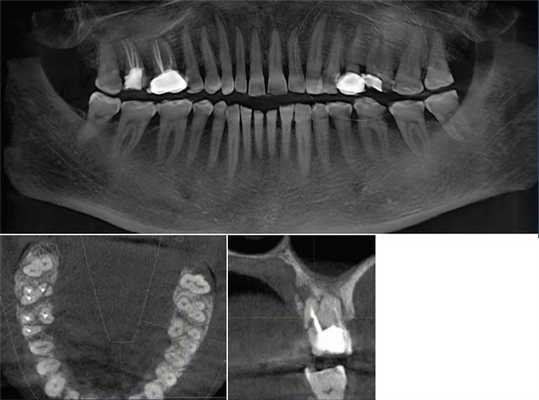

Компьютерная томография в эндодонтии: образец современного лечения

Рентгенография является важным аспектом успешной диагностики одонтогенной и неодонтогенной патологии, лечении пульповой камеры и корневых каналов через коронковый доступ, биомеханической обработки корневых каналов, окончательной обтурации каналов и оценки проведенного лечения. Изображения требуются на протяжении всего эндодонтического лечения. Получение снимка до вмешательства требуется для правильной оценки твердых тканей зуба и альвеолярного отростка, а также степени патологического повреждения и постановки верного диагноза. Далее получение изображений на протяжении всего лечения также является необходимым. Изготовление снимка по окончанию лечения позволяет оценить проведенные манипуляции. Kells впервые сообщил об использование токопроводящего проводника в корневом канале в «радиограмме» в 1899 году.

С тех пор радиология всегда играла ключевую роль в эндодонтии. Теперь, столетие спустя, на основе первых попыток были изобретены компьютерная томография (КТ) и микро-КТ, а презентация в 1996 конусно-лучевой компьютерной томографии (КЛКТ) позволила получать 3D изображения, так необходимые в стоматологической практике.

Эта новая возможность получения изображения в трехмерном измерении значительно повысила уровень терапии в стоматологии по всему миру. КЛКТ постепенно становится золотым стандартом в обеспечении точной постановки диагноза, составления плана лечения и проведения лечения. Конусно-лучевая техника на настоящий момент имеет множество областей применения в стоматологии, это и планирование имплантации, хирургическая оценка патологии, оценка ВНЧС, выявление роста и развития для ортодонтических целей, дооперативная, оперативная и послеоперативная оценка при краниофациальной травме, краниофациальная реконструкция и хирургия полости рта. Вдобавок, КЛКТ используется для выявления точной локализации инородного тела в мягких тканях, выявлении расщепленной губы и неба, а также глубины кариозного поражения. КЛКТ становится типичным инструментом в деятельности хирурга, особенно имплантолога.

КЛКТ в эндодонтии

1. Оценка морфологии корневого канала

Успех эндодонтического лечения зависит от обнаружения всех корневых каналов, а затем их оценки, очистки, обработке и обтурации. Частота встречаемости второго мезиобуккального канала (MB2) в верхних первых молярах варьирует от 69% до 93% в зависимости от выбранного метода исследования. Эта вариабельность возникает в букколингвальной плоскости, где наложение анатомических структур препятствует определению структур с малой разницей в плотности тени. Обычная рентгенография в самом лучшем случае может выявить только 55% этих конфигураций.

Ramamurthy и Matherene описывают ограниченность 2D изображений для определения MB2 каналов (Фото 1).

Фото 1: изображение MB2 в обоих первых молярах

Исследование, проведенное Neelkantan среди индийской популяции, обнаружило, что MB2 канал наиболее типичен для первого верхнего моляра по сравнению со вторым. Также IV анатомический тип канала встречается чаще, чем в монголоидной популяции.

Baratto Filho исследовали внутреннюю морфологию удаленных первых моляров верхней челюсти, сравнивая с данными, полученными при осмотре в микроскоп и при получении изображений КЛКТ ex vivo. Отчеты показали наличие 4-х каналов в 67,14% зубов и дополнительные корневые каналы в 92,85 % случаев в мезиобуккальном корне. Клиническая оценка показала слегка сниженный общий показатель (53,26%), но повышенный показатель выявления MB2 (95,63%), в то время как применение КЛКТ показало 37,05%. Ученые сделали вывод, что КЛКТ является хорошим методом для начальной оценки внутренней морфологии первого верхнего моляр, но для выявления устьев самым оптимальным способом является применение микроскопа. КЛКТ также применялся для выявления высокой встречаемости дистолингвального канала у Тайванцев, выявления аномалий в системе корневых каналов нижних премоляров, и помощи в выявлении искривлении корня (Фото 2).

Фото 2: Аксиальное изображение каналов C-формы во вторых молярах

2. Патологии в периапикальных тканях

Наиболее частым патологическим состоянием, затрагивающим зубы является воспалительные процессы пульпы и периапикальных областей. Технология КЛКТ теперь предоставляет клиницисту возможность обозревать нужную зону в трех различных плоскостях, тем самым получая 3D информацию. Поражения, заключенные в губчатом веществе кости с малым количеством или отсутствием кортикальной пластинки, на обычной пленке могут быть диагностированы с большим трудом. Lofthag-Hansen, Stavropoulos и Wenzel сравнили точность получаемых данных при КЛКТ с ограниченным FOV и обычными снимками.

Ученые сообщили, что КЛКТ предоставляет более точные диагностические данные (61%) по сравнения с цифровыми (39%) и обычными (44%) рентгенограммами. Но, несмотря на то, что данные КЛКТ являются более точными, исследователи не призывают к полному вытеснению обычной внутриротовой рентгенографии для выявления периапикальных изменений в обычной клинической практике из-за финансовой и вредностной составляющих. Estrela и коллеги предложили использовать периапикальные индексы, основанные на КЛКТ, для идентификации патологий (Фото 4-6).

Фото 4: Периапикальная киста в переднем сегменте нижней челюсти

А: 3D изображение, показывающее большую кистозную полость

B: Изображение секционного распила, показывающее утрату кортикальной пластинки

C: Аксиальный вид, демонстрирующий утрату кортикальной пластинки с лабиальной стороны и интактную пластинку с лингвальной.